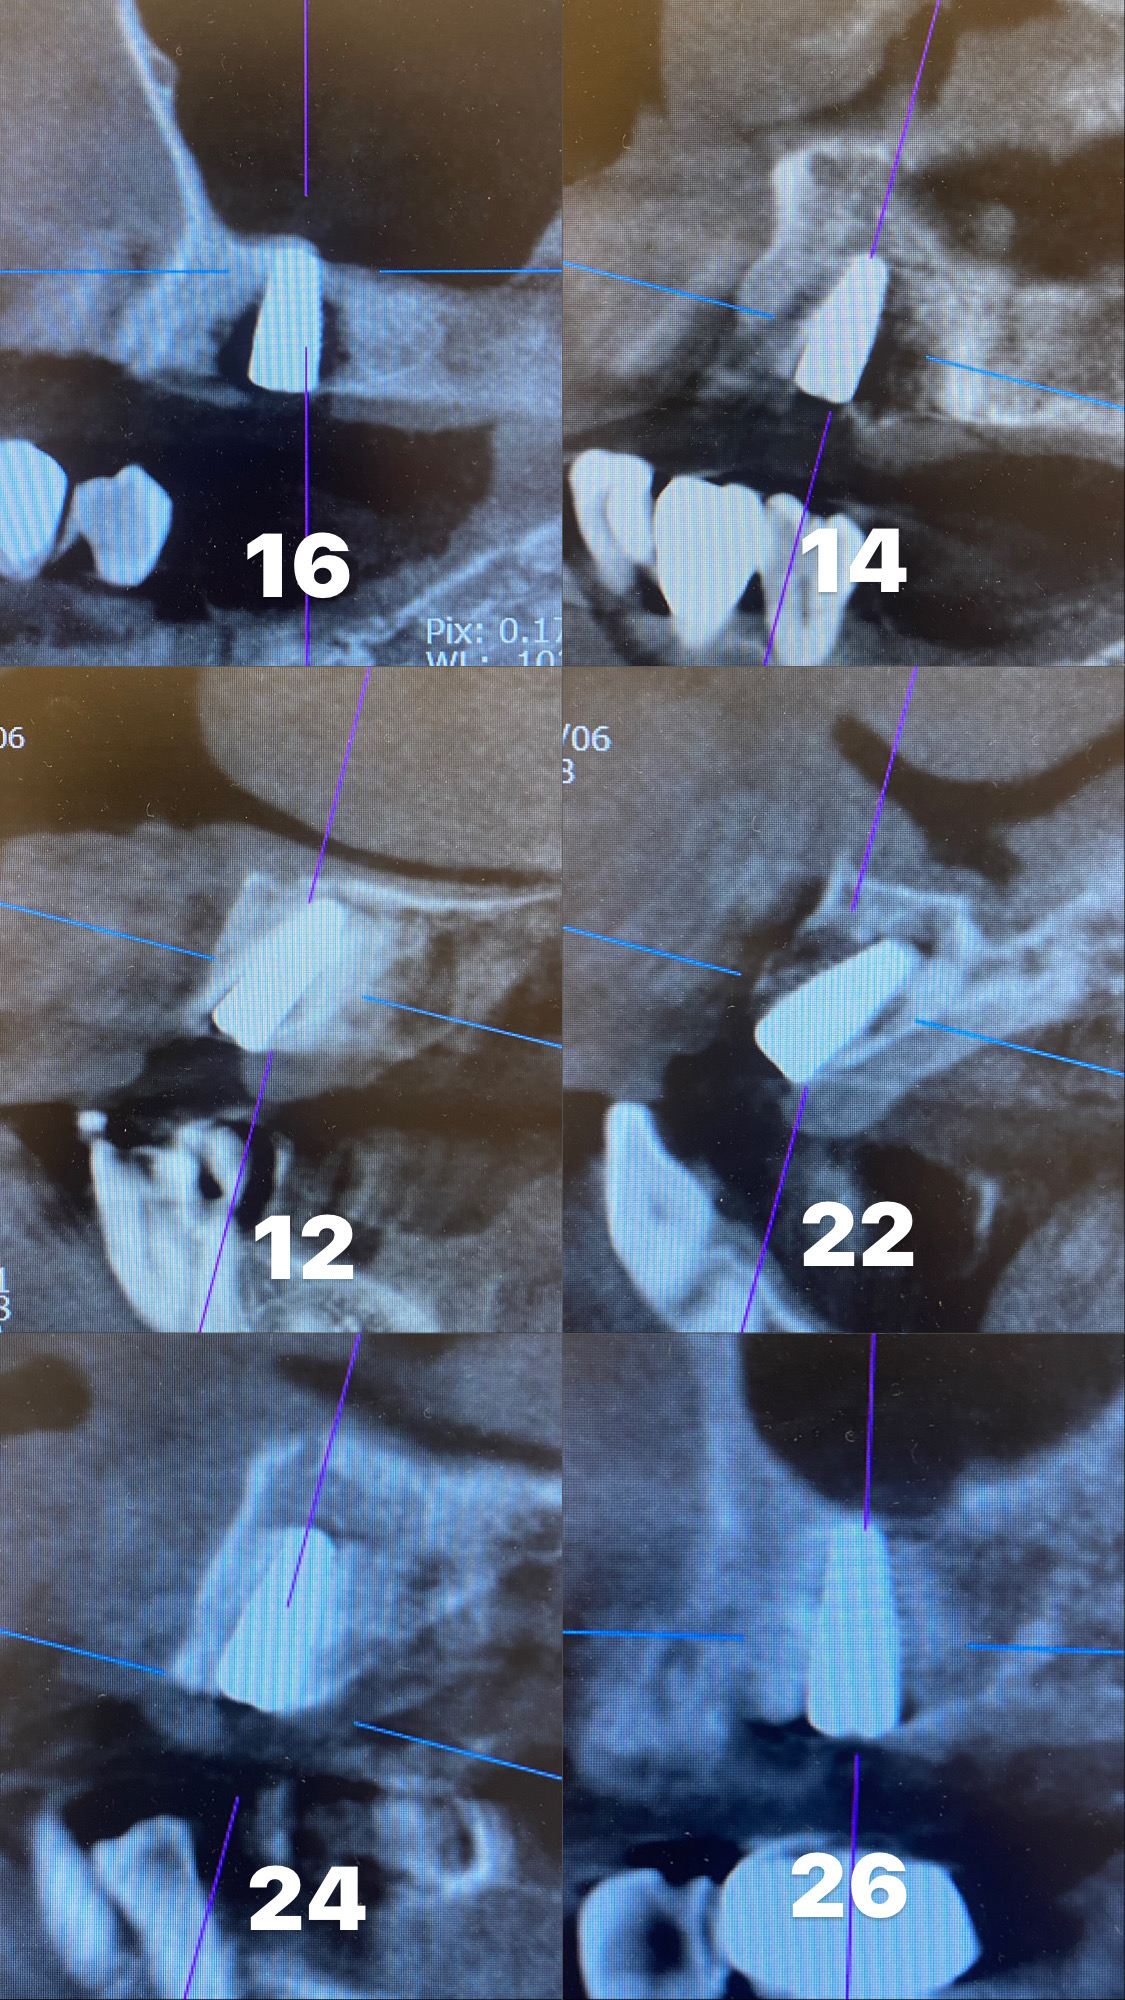

オールオン6のインプラントオペを行いました。

オールオン6とは総入歯で、一本も歯が残っていない顎に支えとなるインプラントを6本埋入しその上に取り外しの不要な被せ物をつける治療となります。